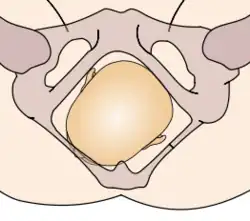

Durante la mecánica del parto, los diámetros menores del feto pasan por los diámetros mayores de la pelvis materna. Con el fin de no quedar encajado en algún punto durante su trayectoria fuera del útero, el neonato pasa por una serie de movimientos naturales que constituyen el mecanismo del parto.

- Descenso: ocurre por acción de la gravedad una vez dilatado el cuello uterino, así como de las poderosas contracciones uterinas y de los músculos abdominales maternos. El descenso tiende a ser lentamente progresivo basado en la estructura pélvica materna.

- Flexión: la cabeza del feto se flexiona, de modo que el mentón fetal hace contacto con su pecho, al encontrarse el primer punto de resistencia del piso pélvico.

- Encajamiento: el diámetro de la cabeza del feto que va desde un hueso parietal al opuesto, llamado diámetro biparietal, alcanza el estrecho superior de la pelvis a nivel de las espinas isquiáticas. Por lo general ocurre en la fase tardía del embarazo, justo al iniciarse el trabajo de parto.

- Rotación interna: ocurre en el estrecho medio de la pelvis, cuando el feto, al continuar su descenso, hace una rotación de 90° en el sentido contrario a las agujas del reloj, de modo de adaptarse a la configuración romboidal de los músculos del piso pélvico, entre el músculo elevador del ano y los ileocoxígeos. Así, la cara del bebé está dirigida mirando hacia el recto materno.

- Extensión: la cabeza del feto atraviesa el canal del parto, se extiende de tal manera que la frente se desplaza primero por el orificio vulvar. La cabeza está por debajo de la sínfisis púbica y ha distendido al máximo el perineo.

- Rotación externa: una vez que ha salido la cabeza, se gira 45° para restaurar su posición original antes de la rotación interna y quedar en posición normal en relación con los hombros. Se denomina por ella la restitución, haciendo el paso de los hombros más factible.

- Expulsión: el hombro púbico tiende a salir primero, seguido por el hombro perineal. El resto del cuerpo sale por sí solo con una leve impulsión materna.

Estos movimientos son todos debido a la relación que existe entre la cabeza ósea y hombros del feto y el anillo óseo de la pelvis materna.

La relación de la fontanela posterior con la pelvis materna determina el diagnóstico de posición. Se distinguen ocho posiciones en la presentación de vértice: I. Occípito ilíaca izquierda anterior (OIIA) en que la fontanela posterior se ubica hacia delante en relación con la pelvis materna y además a la izquierda de la madre. La sutura sagital está orientada oblicuamente. II. Sucesivamente dependiendo de la ubicación de la fontanela posterior (porque la pelvis es siempre la misma) las posiciones serán: